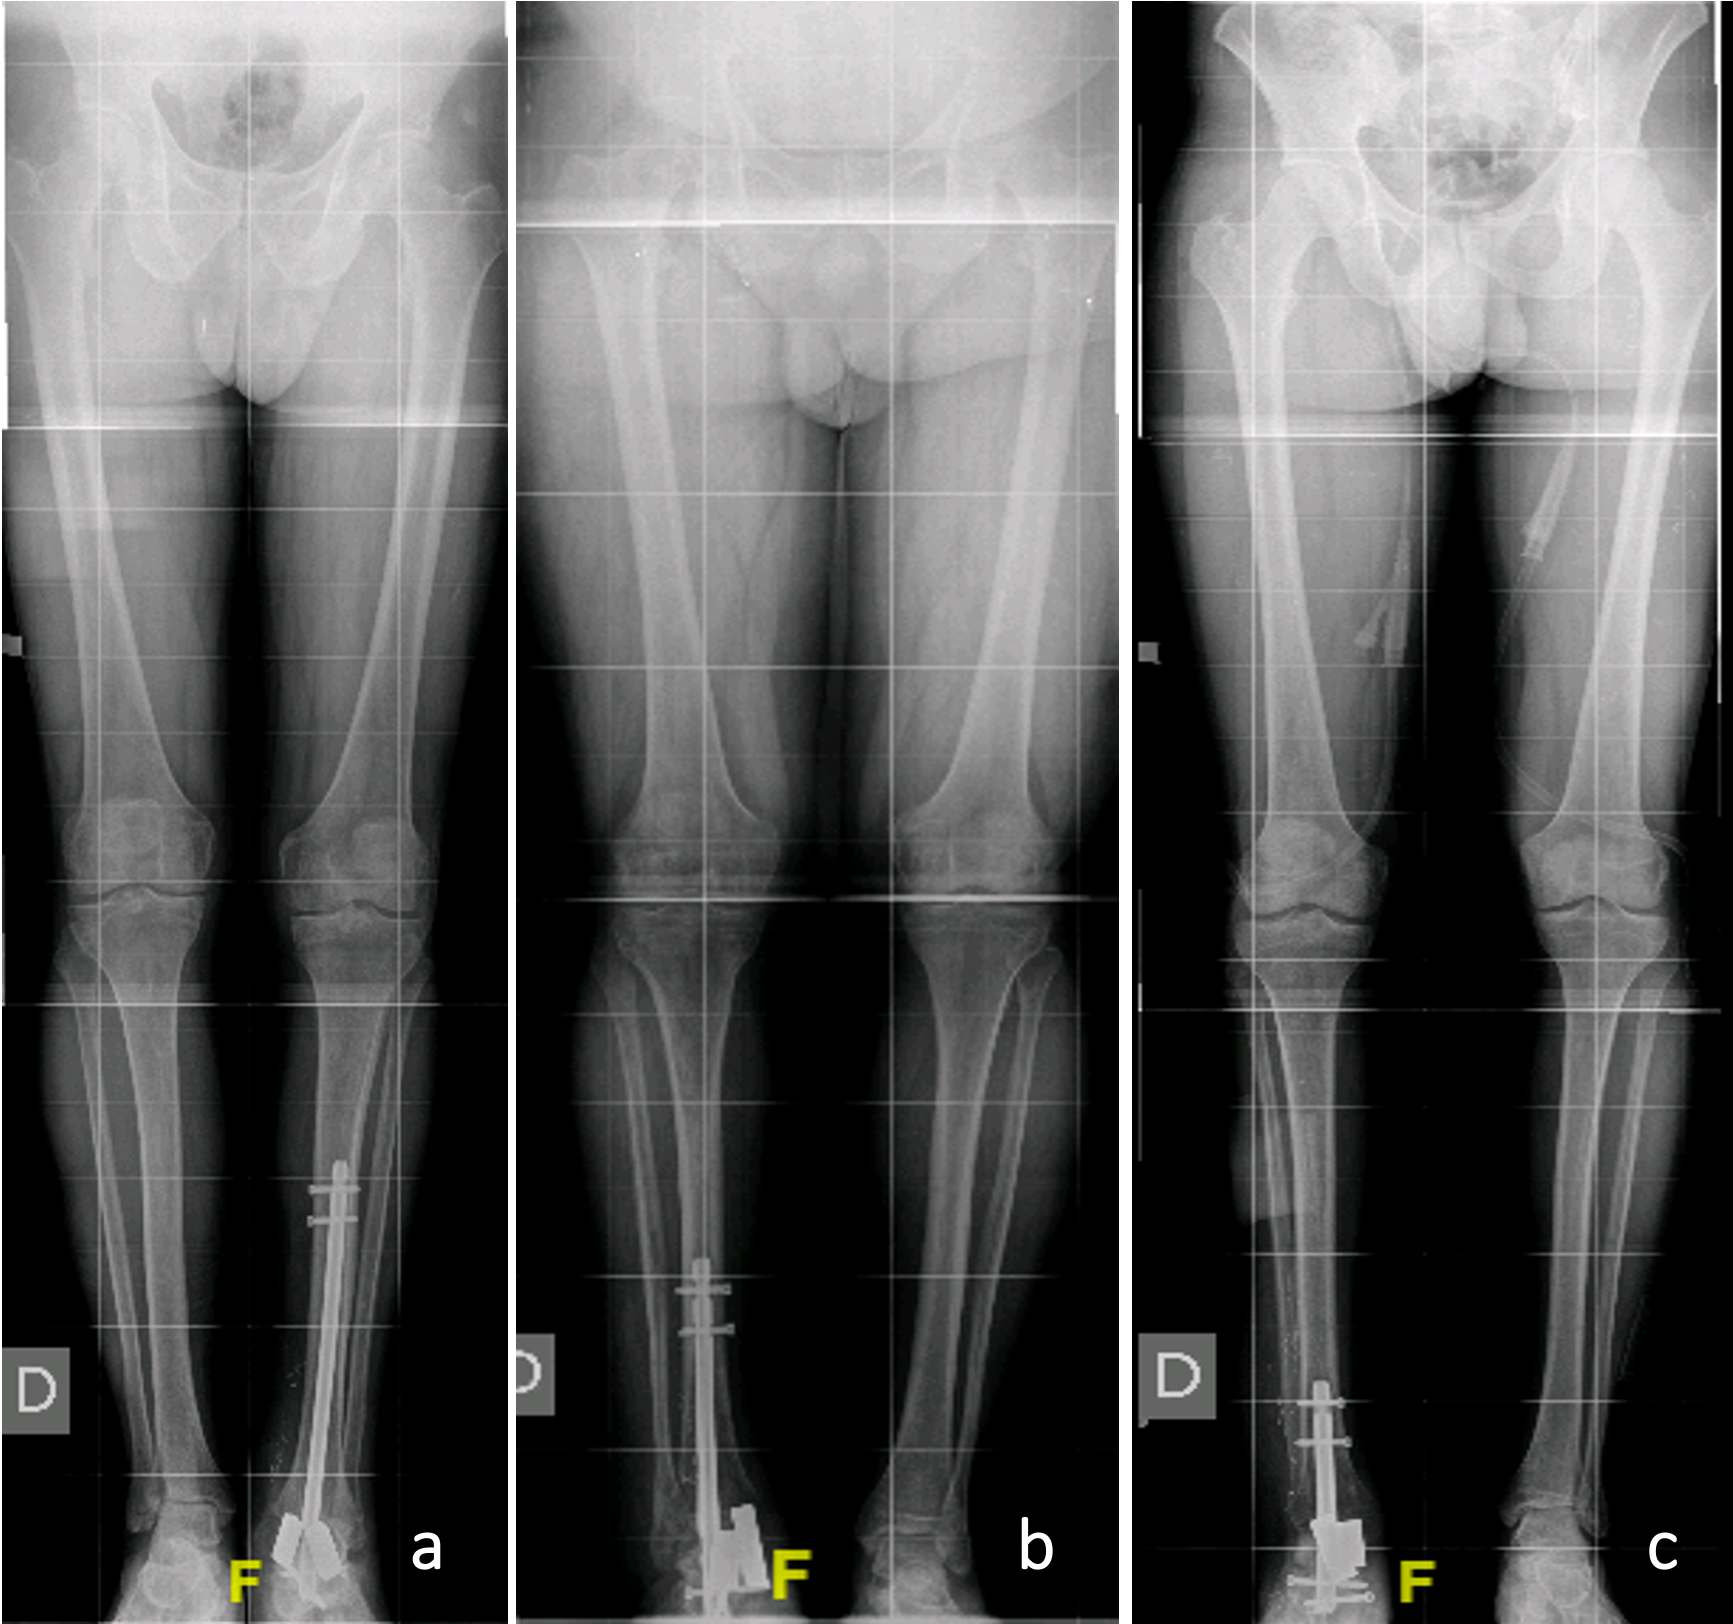

Total fusion was seen in the 1-year follow-up CT scan control, and a correct axis may be seen in X-rays, with no significative leg-length discrepancy (Figs. 3 and 4).

https://jbji.copernicus.org/articles/10/419/2025/jbji-10-419-2025-f03

Figure 3Postoperative alignment. Standing long-leg images corresponding to cases 1 (a), 2 (b), and 3 (c), respectively